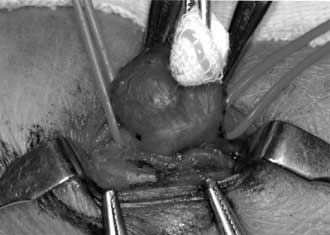

| Fig.

4 |

This

operative photograph shows radial artery aneurysm measuring

17mm in diameter. |